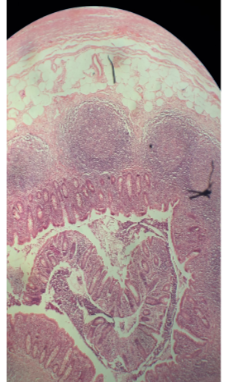

What is this an image of? Name all of the highlighted parts

-Cerebellum

-Arbor vitae

-Cerebral cortex

-Follia (gyrus)

-Pons

-4th ventricle

-Choroid plexus

-Medulla oblongata